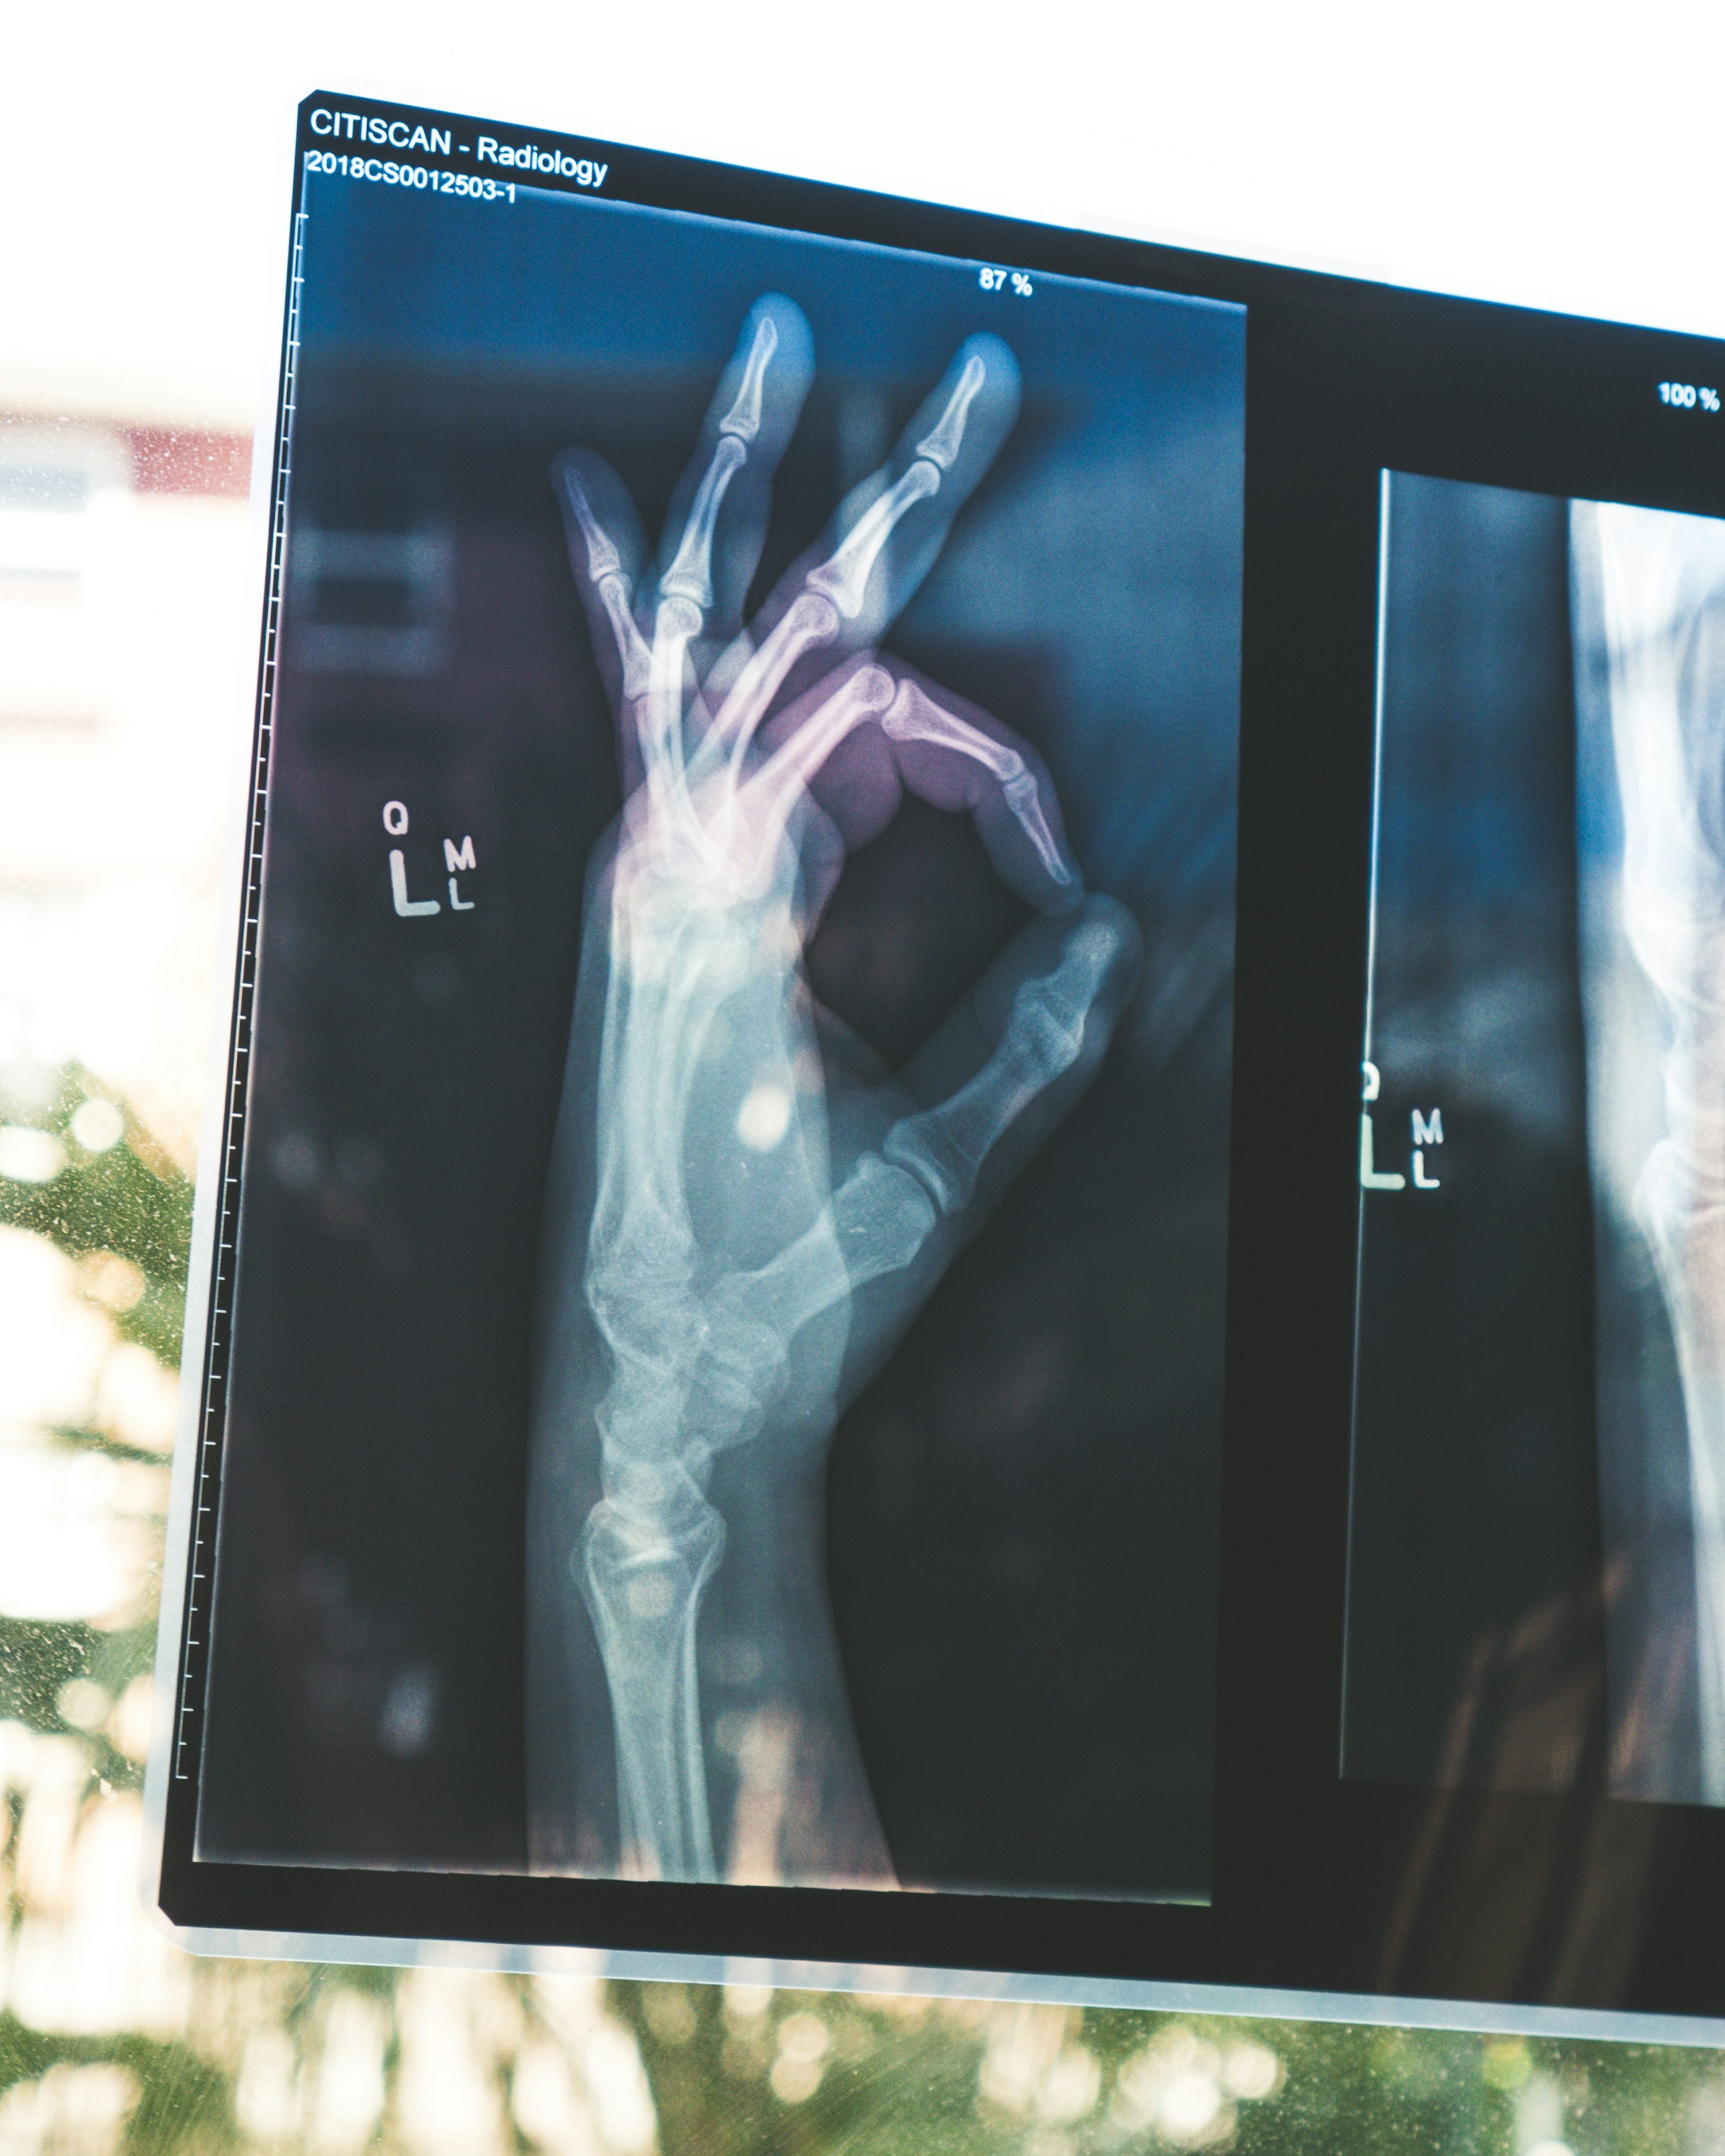

가장 흔한 연관 질환은 목 디스크, 손목터널증후군(수근관증후군), 그리고 당뇨병성 신경병증입니다. 특히 직장인이나 컴퓨터 사용이 잦은 사람에게서 손목터널증후군이 흔히 나타납니다. 이는 손목에 있는 신경이 반복적인 자극을 받아 눌리면서 생기며, 밤에 손이 저려 깨는 경우가 대표적입니다.